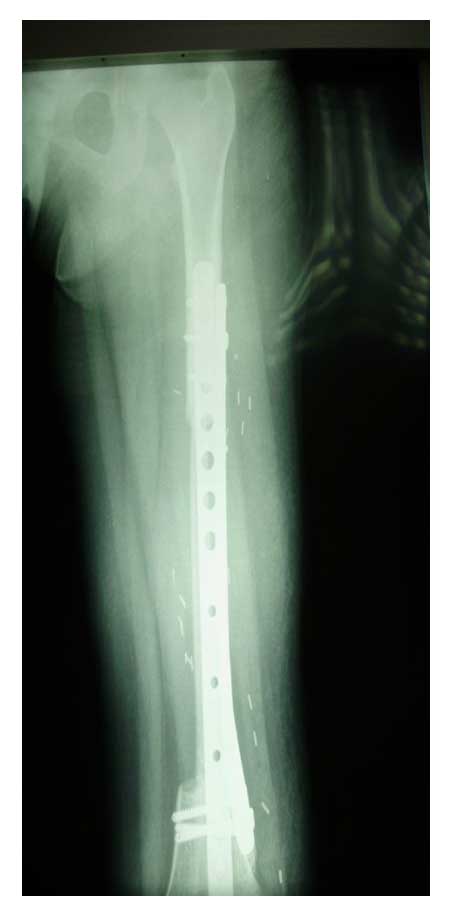

Ameliyat Esnası: Rezeksiyon sonrası vaskülerize fibula uygulanımı ve titanyum plak ile fiksasyon görülmekte.

Ameliyat Sonrası: Röntgende rezeksiyon sonrası vasülerize fibula uygulanımı ve çift plak ile fiksasyon görülmekte.